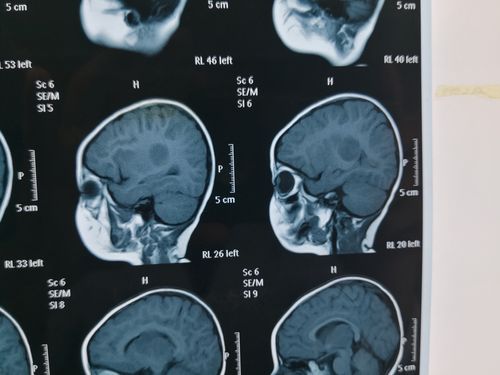

朱育霆 2岁 左侧脑室及丘脑占位 13903809976(副本)

侧脑室磁共振

侧脑室解剖